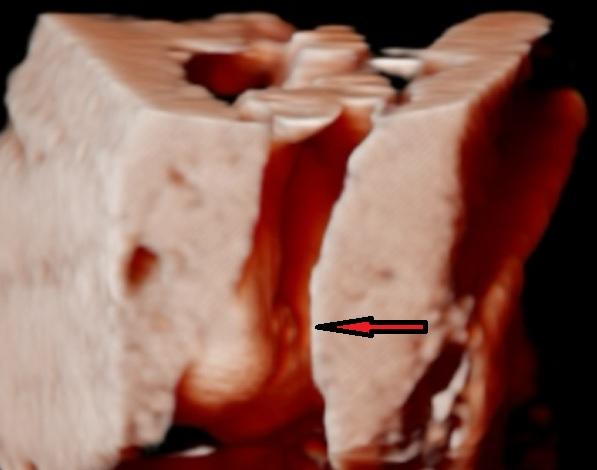

- Na 2D ultrazvuku se jako známky pohlaví často zmiňují „kávové zrno“ (pysky) pro holčičku a „pindík/pindourek“ a varlátka pro chlapečka, přičemž pupeční šňůra a nevhodný úhel snímku jsou časté zdroje omylu.

A: Diskuze uvádí „kávové zrno“ jako znak holčičky (pysky) a „pindík/pindourek“ plus varlátka jako znak chlapečka; uživatelky také zmiňují směr genitálního výběžku (dolů u holek, šikmo dopředu u kluků).

@cybermis to neměla ( šla jsem na něj v době kdy se doporučuje vždy), ale že je tam vidět ta stěna a placenta takhle? Prostě tenhle záběr ořízlej vidim prvně, ale to bude i tou fotkou neostrou... nemusíte se hned čertit, jen už jsem tech utz snímků viděla opravdu dost a tyhle kde je to takhle ořízlé nikdy. Tak se omlouvám, jestli se Vás to nějak dotklo. To je 3d/4d vaginálně ne? Přijde mi jak kdybych viděla pánev Vaší...jen mě to zajímá čistě ze zvědavosti, tohle vážně vidím prvně, vždycky to co nejvíc přibližují a pak tam tohle vidět není, ten okolní "šum".

@cybermis tak 3d je fotka 4d je video, v tom rozdíl není ne? to záleží jen na jasu jestli je to oranžové,nebo ne, to si už nastavuje gyndař-teda mi bylo řečeno, plus samo že jde i o kvalitu přístroje. No nás to čeká za 3týdny po třetí,tak doufám,že snad tam bude někdo schopný, ikdyž kdyby prý ne,tak se platí nějaká minimální částka jenom 🙂